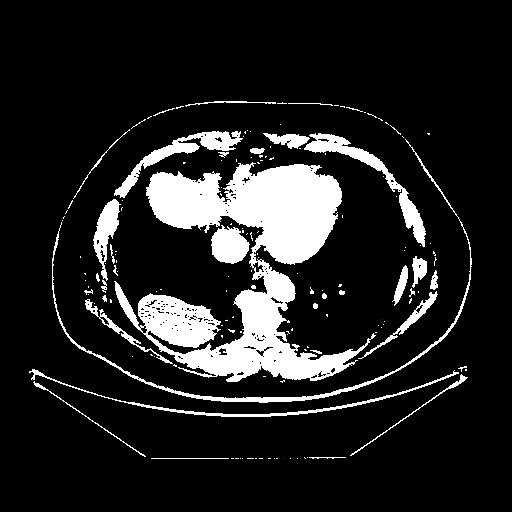

Reconstructed NATIVE CT scan (cycle consistency)

Full window (WL 1023.5, WW 4095 β†’ Low βˆ’1024, High +3071)

Actual HU range: [-1024.0, 3071.0]